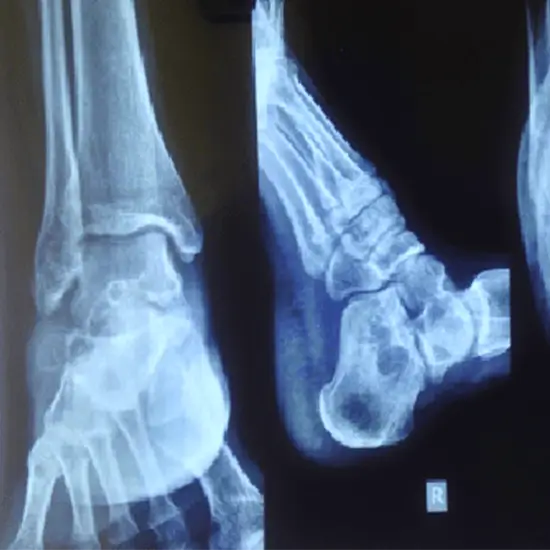

X-Ray Left Ankle AP View

A Left Ankle AP View X-ray reveals the bones of the ankle and the surrounding soft tissues (skin and muscles). The left ankle consists of three bones: the tibia, fibula, and talus (one of the foot bones), as well as two joints: the ankle joint (where the tibia, fibula, and talus meet) and the syndesmosis joint (joint between tibia and fibula).